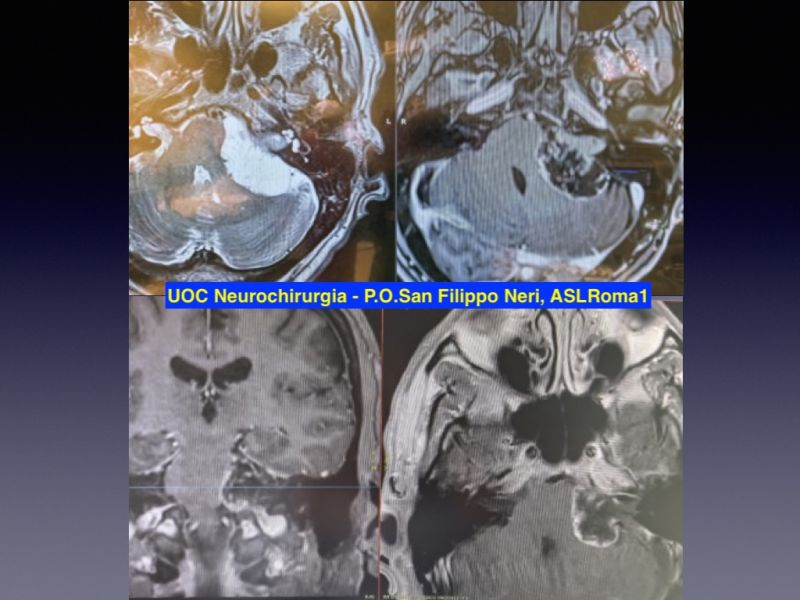

56yo man with severe left hearing loss and moderate ataxia.

MRI: Left Koos IV cystic VS

Microneurosurgical nearly total resection by retrosigmoid approach: a thin layer of the capsule of the cyst, very adherent to the brainstem, was left. It will be followed by serial MRI.